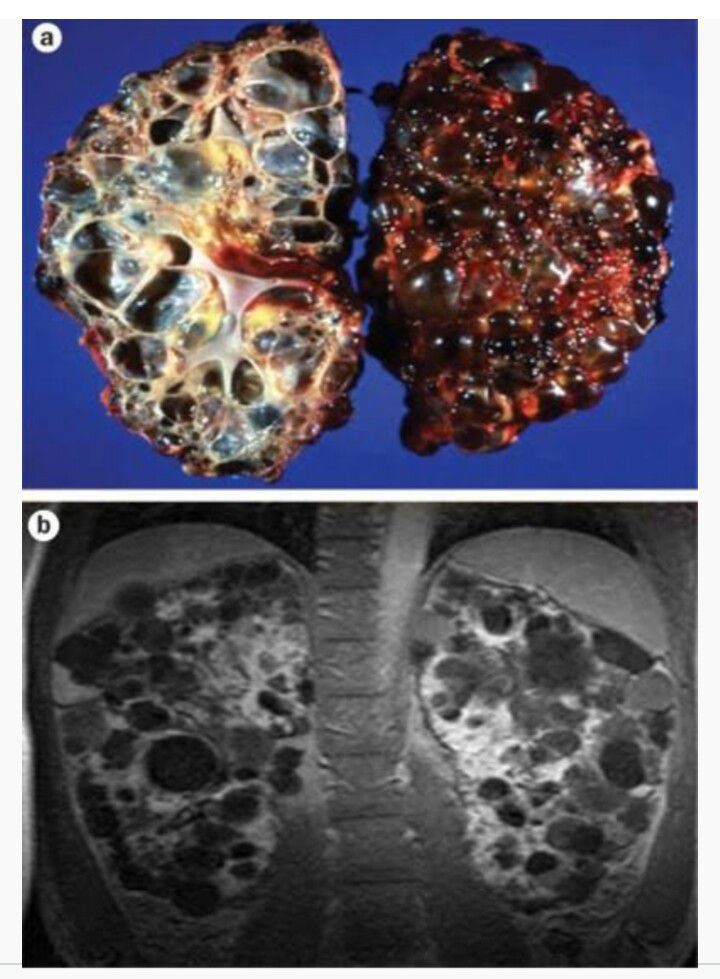

Autosomal dominant polycystic kidney disease (ADPKD) is the most prevalent, potentially lethal, monogenic human disorder. It is associated with large interfamilial and intrafamilial variability, which can be explained to a large extent by its genetic heterogeneity and modifier genes. It is also the most common of the inherited cystic kidney diseases — a group of disorders with related but distinct pathogenesis, characterized by the development of renal cysts and various extrarenal manifestations, which in case of ADPKD include cysts in other organs, such as the liver, seminal vesicles, pancreas, and arachanoid membrane, as well as other abnormalities, such as intracranial aneurysms and dolichoectasias, aortic root dilatation and aneurysms, mitral valve prolapse, and abdominal wall hernias. Over 50% of patients with ADPKD eventually develop end stage kidney disease and require dialysis or kidney transplantation.